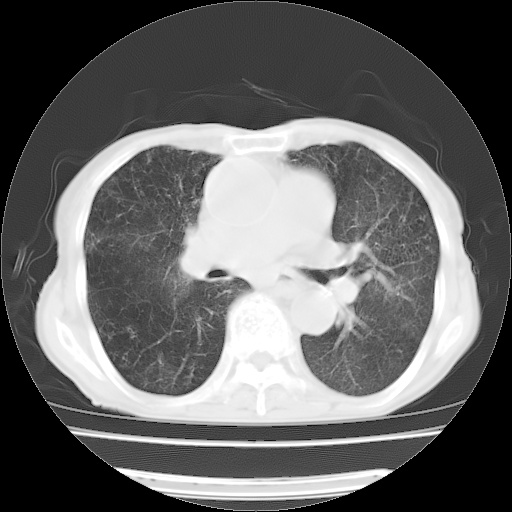

病人发热、气促就诊。原二周前已行ct扫描,当时诊断为双肺下叶、右肺中叶支气管扩张并感染,双肺上叶片状渗出性病变。今天复查胸部ct,双肺下叶支气管扩张并感染病灶较前明显吸收,但双肺上叶渗出性病变较范围较前明显增大。

现传今天ct图像给大家讨论。

双肺多发大片状、斑片状高密度渗出影,部分实变,考虑病毒性肺炎。